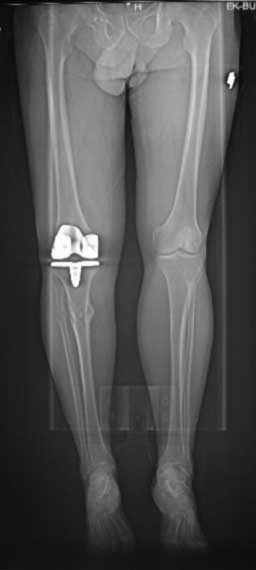

У пациента 50 лет имеется разгибательная контрактура через 8 меспосле ТКА. Уважаемые коллеги. Пациент 8 мес после операции ТКА, в анамнезе – неправильно сросшийся перелом голени, коррекция оси (снимки прилагаются. В настоящее время имеется разгибательная контрактура 10/5/0, на операционном столе было 90/0/5, на момент выписки движения 50/0/0 в надежде на дальнейшую разработку. До эндопротезирования 40/10/0. Глубокая инфекция исключена. Ротация бедренного компонента в норме (по КТ). Вопросы: насколько для такого ограничения критична некорректная установка б/б компонента (я намерял 7 град)? Причина нынешнего состояния, артрофиброз? Какие действия следует предпринять, удаление рубцов, релиз головок 4-главой мышцы? Что-либо другое, ваше мнение? С уважением, Максим Агалаков, Екатеринбург.